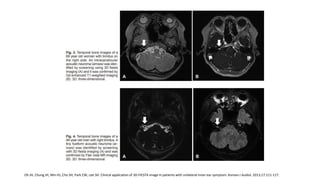

RM

Sensibilidad del 100%

• Gold estándar: T1 realce con contrate.

• Imágenes ponderadas en T2

• CISS o FIESTA

RM Sensibilidad del 100% •Gold estándar: T1 realce con contrate. • Imágenes ponderadas en T2 • CISS o FIESTA Abele TA, Besachio DA, Quigley EP, et al. Diagnostic accuracy of screening MR imaging using unenhanced axial CISS and coronal T2WI for detection of small internal auditory canal lesions. Am J Neuroradiol. 2014;35:2366-2370. Oh JH, Chung JH, Min HJ, Cho SH, Park CW, Lee SH. Clinical application of 3D-FIESTA image in patients with unilateral inner ear symptom. Korean J Audiol. 2013;17:111-117. American Academy of Otolaryngology–Head and Neck Surgery. Clinical Practice Guideline: Sudden Hearing Loss (Update). Otolaryngology– Head and Neck Surgery 2019, Vol. 161(1S) S1–S45 Cadoni G, Cianfoni A, Agostino S, et al. Magnetic resonance imaging findings in sudden sensorineural hearing loss. J Otolaryngol. 2006;35:310-316.

• FIESTA Sensibilidad: 84.6%-98% Especificidad:96-100% IC 95% interobservador Ordóñez L. VALIDACIÓN DE UNA PRUEBA DIAGNÓSTICA: SECUENCIA FIESTA DE IMÁGENES DE RESONANCIA MAGNÉTICA EN SCHWANOMA VESTIBULAR. Rev.Medica.Sanitas 15 (4): 18-25, 2012